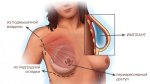

Соски уже ниже ватерлинии

Еще

Плохо что ли?

Тут непонятно, но когда вниз смотрят, это хуйня, конечно. Когда они сильно низко, но смотрят вперед-вверх, пойдет.

Да нормально для милфы.

Это уже птоз.

И там консервативными методами уже не отделаться...

Вот хуй блеать поймешь: то ли это сиськи натурально разъехались, то ли это импланты.

Мне хочется сказать, что у неё мышечные импланты, но сомневаюсь.

Нет у нее имплантов.